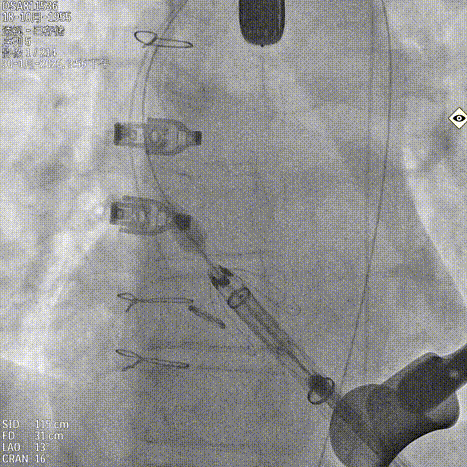

基于瓣环及瓣上结构的锚定条件,手术团队选择 JS/TAVI-31 瓣膜进行植入。术中团队配合默契。鉴于主动脉瓣上空间有限,手术在瓣环位置释放定位件后送入瓣上并尝试入窦。得益于输送器独特的调弯设计,仅经两次尝试即顺利进入窦内并完成瓣膜释放,器械操作时间仅 8 分钟。手术过程中,团队通过右冠窦居中造影、定位件入窦确认,以及释放后超声联合造影评估,多重手段保障瓣膜定位精准、释放过程平稳,整体手术流程按术前预演顺利完成。术中超声评估未见瓣周漏,血流动力学表现良好,手术顺利结束。

释放瓣膜

锁丝脱钩

撤出输送器

术后造影 反流消失